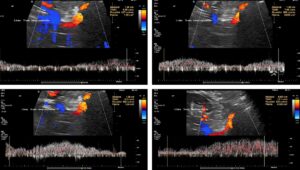

Blood within the tronc réno-rachidièn is modulated in a pulsatile manner, demonstrating rhythmic compression of the left renal vein between the aorta and superior mesenteric artery. This compression is so pronounced that no blood flow is visible ventral to the aorta only the pressure wave is transmitted towards the collateral vessel.

This image demonstrates the transfer of the pulsatile pressure of the aorta and the superior mesenteric artery towards the tronc réno-rachidièn (yellow arrows). Both arteries completely squeeze the final portion of the left renal vein obstructing the entire blood flow, but the pressure is rhythmically transferred towards the spinal canal and thus the spinal cord. Not rarely affected patients develop headaches and migraines which was not the case in this patient.

These images show the respiratory variability of volume transport within the tronc réno-rachidèn.